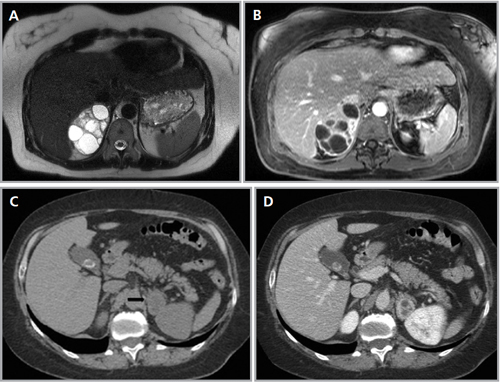

Los valores más utilizados son un 40% de lavado relativo de en fase tardía realizada a los 15 minutos y un lavado absoluto de 60%. De este modo cualquier lesión que muestre un lavado relativo mayor al 40% o absoluto mayor al 60% es consistente con un adenoma, con una sensibilidad y especificidad cercana al 100% (Figura 14 a, b y c). Dado la rapidez con que se obtiene un TAC de abdomen en la actualidad, algunos trabajos han recomendado utilizar cortes tardíos realizados a los 10 minutos, con el fin de optimizar el tiempo de examen, y utilizar un valor relativo de corte más conservador del 50%9.

A

B

C Figura 14. Tomografía computada de un adenoma suprarrenal izquierdo típico. Se ha colocado un circulo que representa la región de interés en la lesión de la glándula suprarrenal izquierda, obteniendo una medición promedio (Avg) expresada en unidades Hounsfield (UH). En fase precontraste (a) su densidad es de 0 UH, (flecha), en fase protovenosa (b) alcanza una densidad de 59 UH (cabeza de flecha), y en fase tardía (c) su lavado es de aproximadamente un 50%, llegando a una densidad de 30 UH.